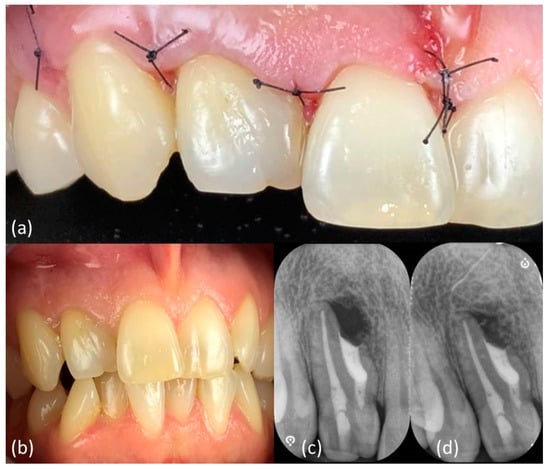

The shaping was performed following the ProtaperGoldTM sequence (Dentsply Maillefer, Charlotte, VA, USA), to size F1 20/.08, to minimize root canal transportation (Figure 4a). The working length was 19 mm confirmed by an electronic apex locator (Dentsply Sirona, Charlotte, VA, USA). Irrigation was performed through a flexible plastic 30-gauge needle (IrriFlex®, Produits Dentaires, Vevey, Switzerland) using 5% sodium hypochlorite solution (Niclor 5, OGNA, Pavia, Italy), followed by 17% ethylenediaminetetraacetic acid (EDTA 17%, OGNA, Pavia, Italy) (Figure 4b). Passive ultrasonic irrigation was carried out using a cordless ultrasonic unit with a flexible tip (EndoUltraTM, MICRO-MEGA®, Besançon Cedex, France). Finally, the canal was filled with warm gutta-percha vertical technique using cordless units (Fast Pack and Fast Fill, Eighteeth, Shangai, China) (Figure 4c). The access cavity was restored with an adhesive composite restoration (Figure 4d). A final post-operative LCPA X-ray was taken (Figure 4e) (Movie 4). At the same appointment, a flap was opened (Figure 4f) and the granulomatous tissue extending above the invagination and the main canal foramen was surgically removed (Figure 4g,h).

Main clinical steps of case 1. Orthograde approach: (a) shaping with rotary files, (b) irrigation with a plastic needle, (c) gutta-percha filling, (d) conservative coronal restoration and (e) periapical X-ray. Surgical approach: (f) Surgical flap design, (g) granulomatous tissue removal, (h) resulting invagination access exposure which was prepared with ultrasonic tips and irrigated with a plastic needle, (i) 3D-invagination filling with a putty bioceramic sealer and (j) periapical X-ray after palatal and buccal membrane positioning.

The invagination was prepared with ultrasonic tips (KiS, Obtura Spartan Endodontics, Algonquin, IL, USA) and irrigated with a sterile saline solution (Sodium Chloride 0.9%, Fresenius Kabi, Bad Homburg, Germany) carried by a plastic needle. For the retrograde filling, a bioceramic sealer (EndoSequence BC RRM Fast Set Putty, Brasseler USA®, Savannah, GA, USA) was delivered with a syringe (Figure 4i). A microsurgical mirror (BLACK ULTRAmicro B6183, Hahnenkratt, Koginbach Stein, Germany) (Figure 4h) was used to confirm under microscope magnification the retro-preparation and plugging stages. Palatal and buccal absorbable collagen membranes (Ossix® Plus, Sweden&Martina, Padova, Italy) were positioned prior to flap reapproximation and closure with an absorbable 5-0 suture (Movie 5). A post-surgical LCPA X-ray was taken (Figure 4j).

One week later, no discomfort has been reported and primary tissue healing had been achieved, allowing sutures removal (Figure 5a). Clinical (Figure 5b) and radiographic follow-up (Figure 5c,d) showed a positive outcome, with soft tissue and bone healing progression.

Tissue healing after (a) one week and (b) six months and (c) six-months and (d) twelve-months radiographic follow-up.